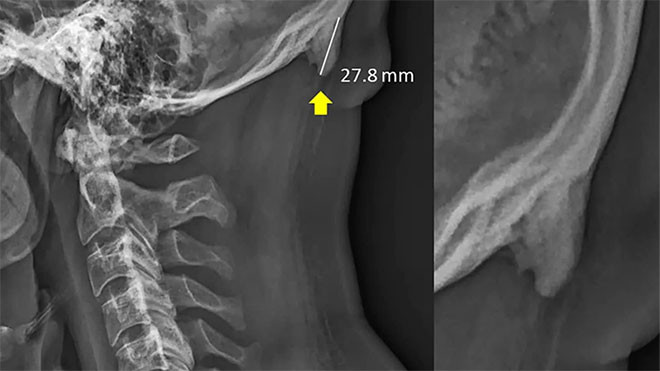

Bu da tendon ve bağlardaki bazı kemiklerin büyümesine ve kafatasının arkasında boynuz benzeri çıkıntıya yol açıyor.

18-36 yaş aralığındaki yaklaşık 400 kişinin röntgenini inceleyen araştırmacılar, bu çıkıntıların gençlerde çok, yaşlılarda ise az bulunduğunu belirtti.